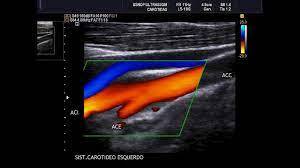

Análise das artérias que levam o sangue do coração para a cabeça. Procuramos por espessamento das paredes, placas de gordura que possam causar entupimentos, tortuosidade, além de dissecções (quando há descolamento da camada mais interna da artéria) e nódulos na bifurcação das carótidas. O estudo pós-procedimento, como retirada cirúrgica das placas de gordura e colocação de stent também é realizado por este método. As alterações de fluxo das artérias vertebrais também são facilmente identificadas por este exame.